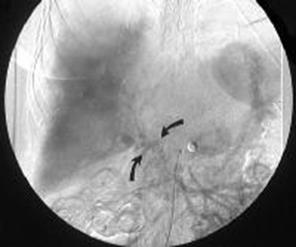

В части случаев очень полезные данные может дать ангиография (см. Рисунок 4).

Рисунок 4. Тромбоз воротной вены. С помощью цифровых методик выделен кровоток по воротной вене при проведении ангиографии через верхнюю брыжеечную вену. Четко визуализируются коллатерали, но самой воротной вены не видно. Следует отметить, что печень отделена от грудной клетки из-за скопившейся жидкости при асците. У пациента развилась тяжелая печеночная недостаточность, и он умер через 3 суток после проведения ангиографии. На аутопсии выявлен ранний цирроз печени, фульминантный гнойный холангит, множественные абсцессы печени, тромбоз воротной вены, селезеночной и левых желудочных вен. [по материалам www.emedicine.com]